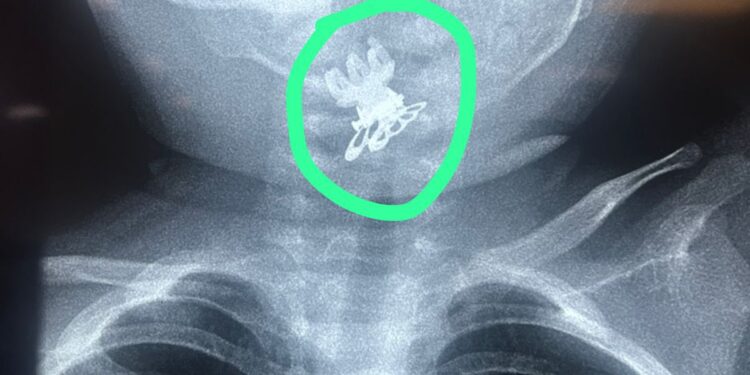

تمكّن فريق طبي في مدينة الصدر الطبية من إنقاذ حياة طفلة بعمر سنة ونصف بعد تعرضها لحالة اختناق شديدة نتيجة ابتلاعها مشبك شعر (قرّاصة) استقر في مدخل المجرى التنفسي.

وأوضحت الطبيبة الاختصاص جراحة الأنف والأذن والحنجرة الدكتورة فرقان حميد محمد” أن الطفلة أُدخلت إلى صالة عمليات الطوارئ وهي تعاني من اختناق وسعال شديدين وعلى الفور تم إجراء الفحوصات والأشعة اللازمة التي أظهرت وجود جسم غريب في مدخل المجرى التنفسي.